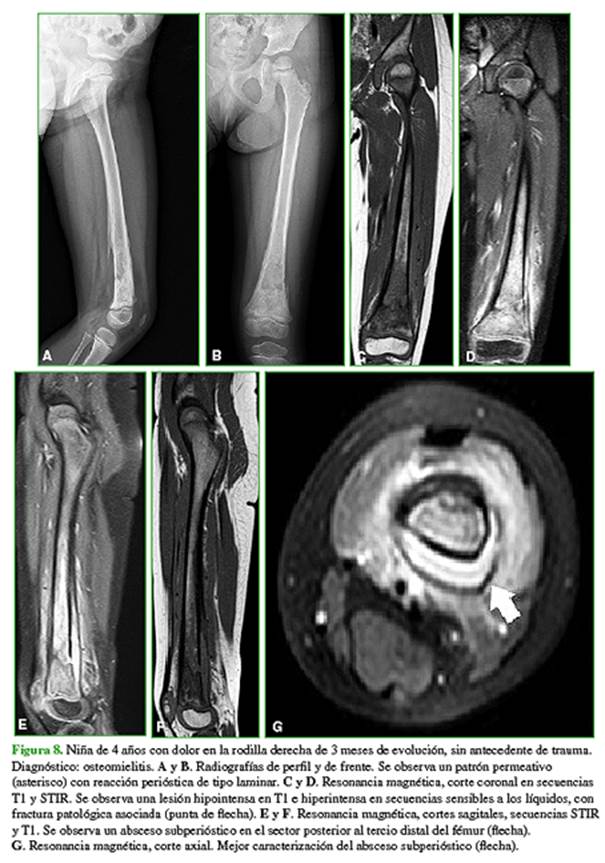

Los diagnósticos diferenciales más frecuentes son: sarcoma de Ewing y osteomielitis (Figuras 7 y 8).